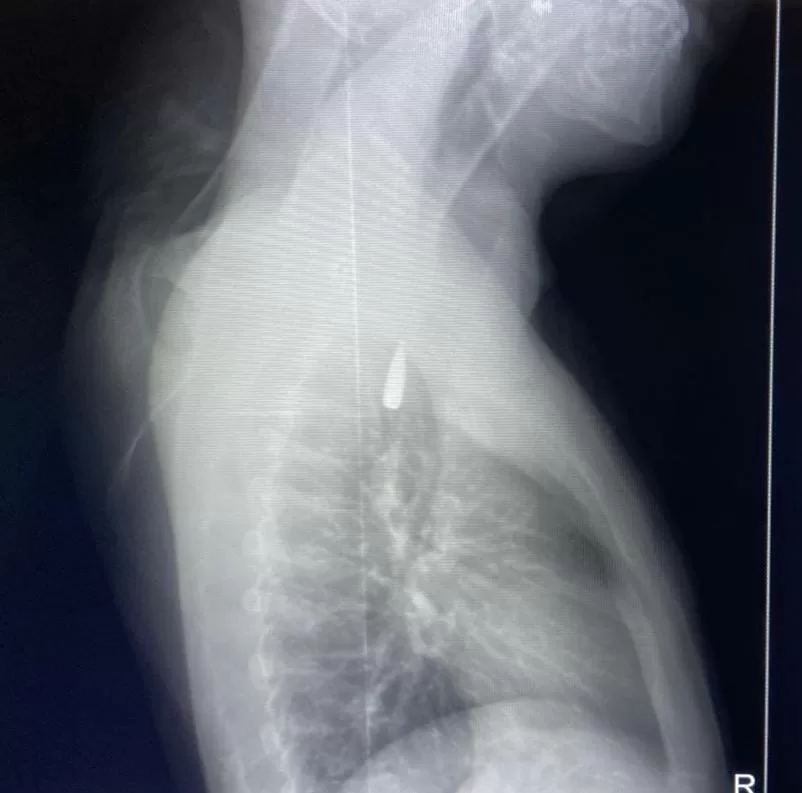

وأوضح الدكتور تامر عبد الله، عميد كلية الطب ورئيس مجلس إدارة المستشفيات الجامعية، أنه في يوم 21 أكتوبر 2025 تمكن فريق من أطباء قسم جراحة القلب والصدر والتخدير والمعاونين من إجراء جراحة دقيقة بالغة الخطورة لأحد المرضى المحجوزين من قطاع غزة، والذي كان قد تعرض لإصابة بطلق ناري في الرأس منذ فترة، استقر المقذوف على إثرها داخل تجويف القفص الصدري قرب الشريان الأورطي، وهو أكبر وأهم شرايين الجسم والمسؤول عن تغذية جميع الأعضاء الحيوية، وأضاف أن الفريق الطبي، رغم دقة الحالة وتعقيدها، نجح في استخراج المقذوف بأمان بعد عملية جراحية نادرة استمرت عدة ساعات داخل المستشفى الجامعي الجديد، حيث خضع المريض بعدها للرعاية الطبية اللازمة، وحالته حاليًا مستقرة وتحت المتابعة الدقيقة من الفريق المختص.